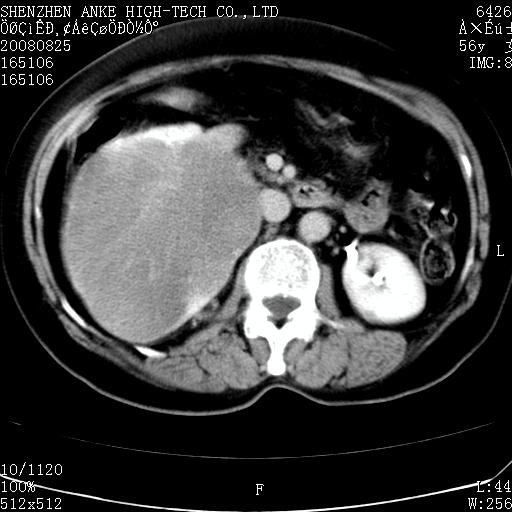

患者,女性,56岁,腰痛3年,查:右腹部约8x10cm肿块,固定,无压痛;8月23日在外院做了平扫,发现右肾巨大肿块(外院具体诊断不祥);今天在我院做了静脉肾盂造影,示:右肾明显增大,分泌功能明显减弱。

1)考虑右肾癌并右肾静脉瘤栓形成。2)脂肪肝。